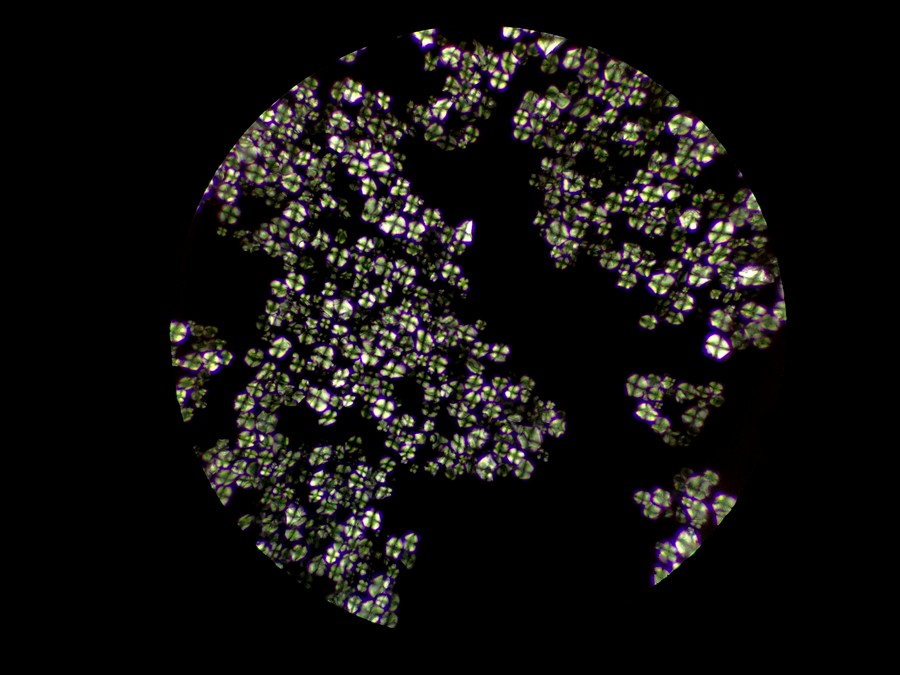

偏光下的中藥顆粒

偏光觀察是對結晶物質的形態進行觀察和測量的一種技術,在生物顯微鏡ML31基礎上加入偏光附件,即可升級為簡易偏光顯微鏡ML31-P,正交偏光下可以看到顆粒出現了偏光反應,形成以粒心為中心的黑色“十”字外觀,這是淀粉粒的典型特征。

在其他視野中,我們也看到了一些其他偏光反應,可能是草酸鈣簇晶之類成分,也可能是玻片或者水中的雜質。